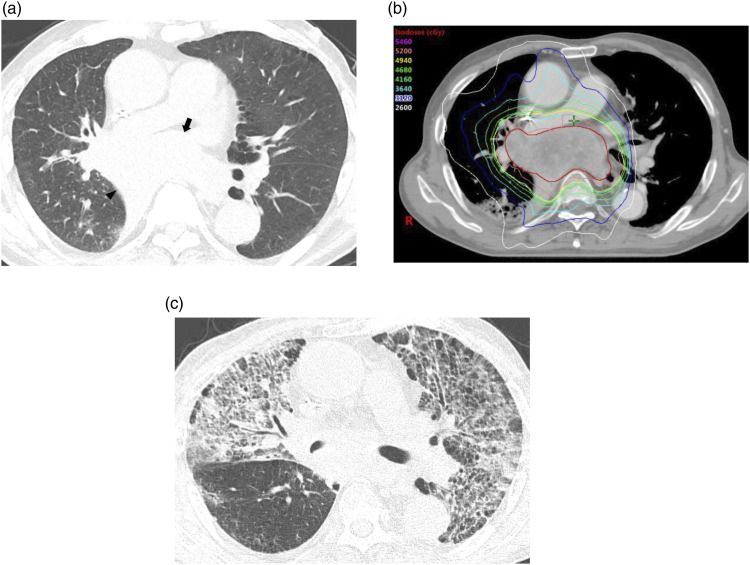

Materials and methods: We reviewed data from 240 NSCLC patients who underwent RT between 2014 and 2022. CT findings of RP were evaluated for parenchymal abnormalities and distribution, which were then classified into three patterns: localized pneumonia (LP), cryptogenic organizing pneumonia (COP), and acute interstitial pneumonia (AIP). Clinical outcomes of RP were evaluated based on Common Terminology Criteria for Adverse Events (CTCAE) grade.

Results: Of the 153 patients, 135 developed RP. The most common pattern was LP (n = 78), followed by COP (n = 30) and AIP (n = 25). Among the three CT patterns, CTCAE grade and days between the start of RT and the onset of RP (RT-RP days) were statistically significantly different (p < 0.05). The patients with AIP patterns exhibited higher CTCAE grade, and fewer RT-RP days compared to those with non-AIP patterns (p < 0.05). In these patients, lung-to-lung metastasis and underlying interstitial lung abnormality were observed more frequently (p < 0.05). Underlying pulmonary fibrosis, the AIP pattern, and higher CT extent scores were more frequently observed in higher CTCAE grade group (p < 0.001). In multiple regression analysis, age, bilateral distribution, RT-RP days, and CT extent score ≥3 were independent predicting factors for higher CTCAE grade.

Conclusions: RP in NSCLC patients can be classified into LP, COP, and AIP patterns and they exhibit different severities in clinical outcomes.